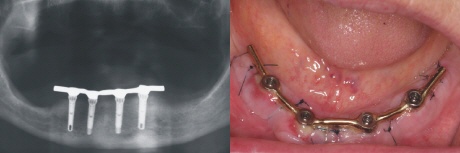

Versorgung

Im zahntechnischen Labor ist innerhalb von einem Tag mit vorgefertigten Teilen (konfektionierten Teilen) ein Steg hergestellt worden, der einen Tag nach der Implantation auf die Implantate aufgeschraubt wird. Die Röntgenkontrolle (links) zeigt den exakten Sitz des Steges auf den Implantaten.

Im Mund zeigt sich eine dezente Schwellung der Schleimhaut um die eingeschraubte Stegkonstruktion (rechts im Bild).